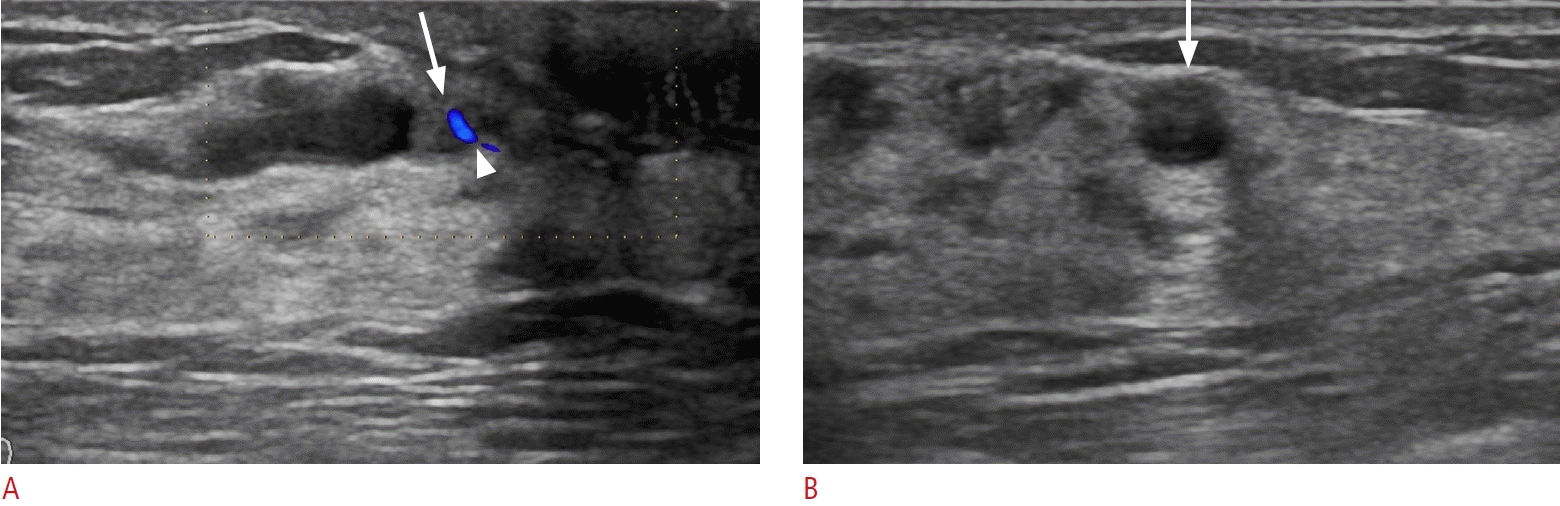

32. Okuno T, Watanabe T, Yamaguchi T, Konno S, Takaki R, Watanabe R, et al. Usefulness of color Doppler and strain elastography adjunctive to B-mode ultrasonography in the diagnosis of nonmass abnormalities of the breast: results of the BC-07 multicenter study of 385 cases. J Med Ultrason (2001). 2025; 52:157–168.